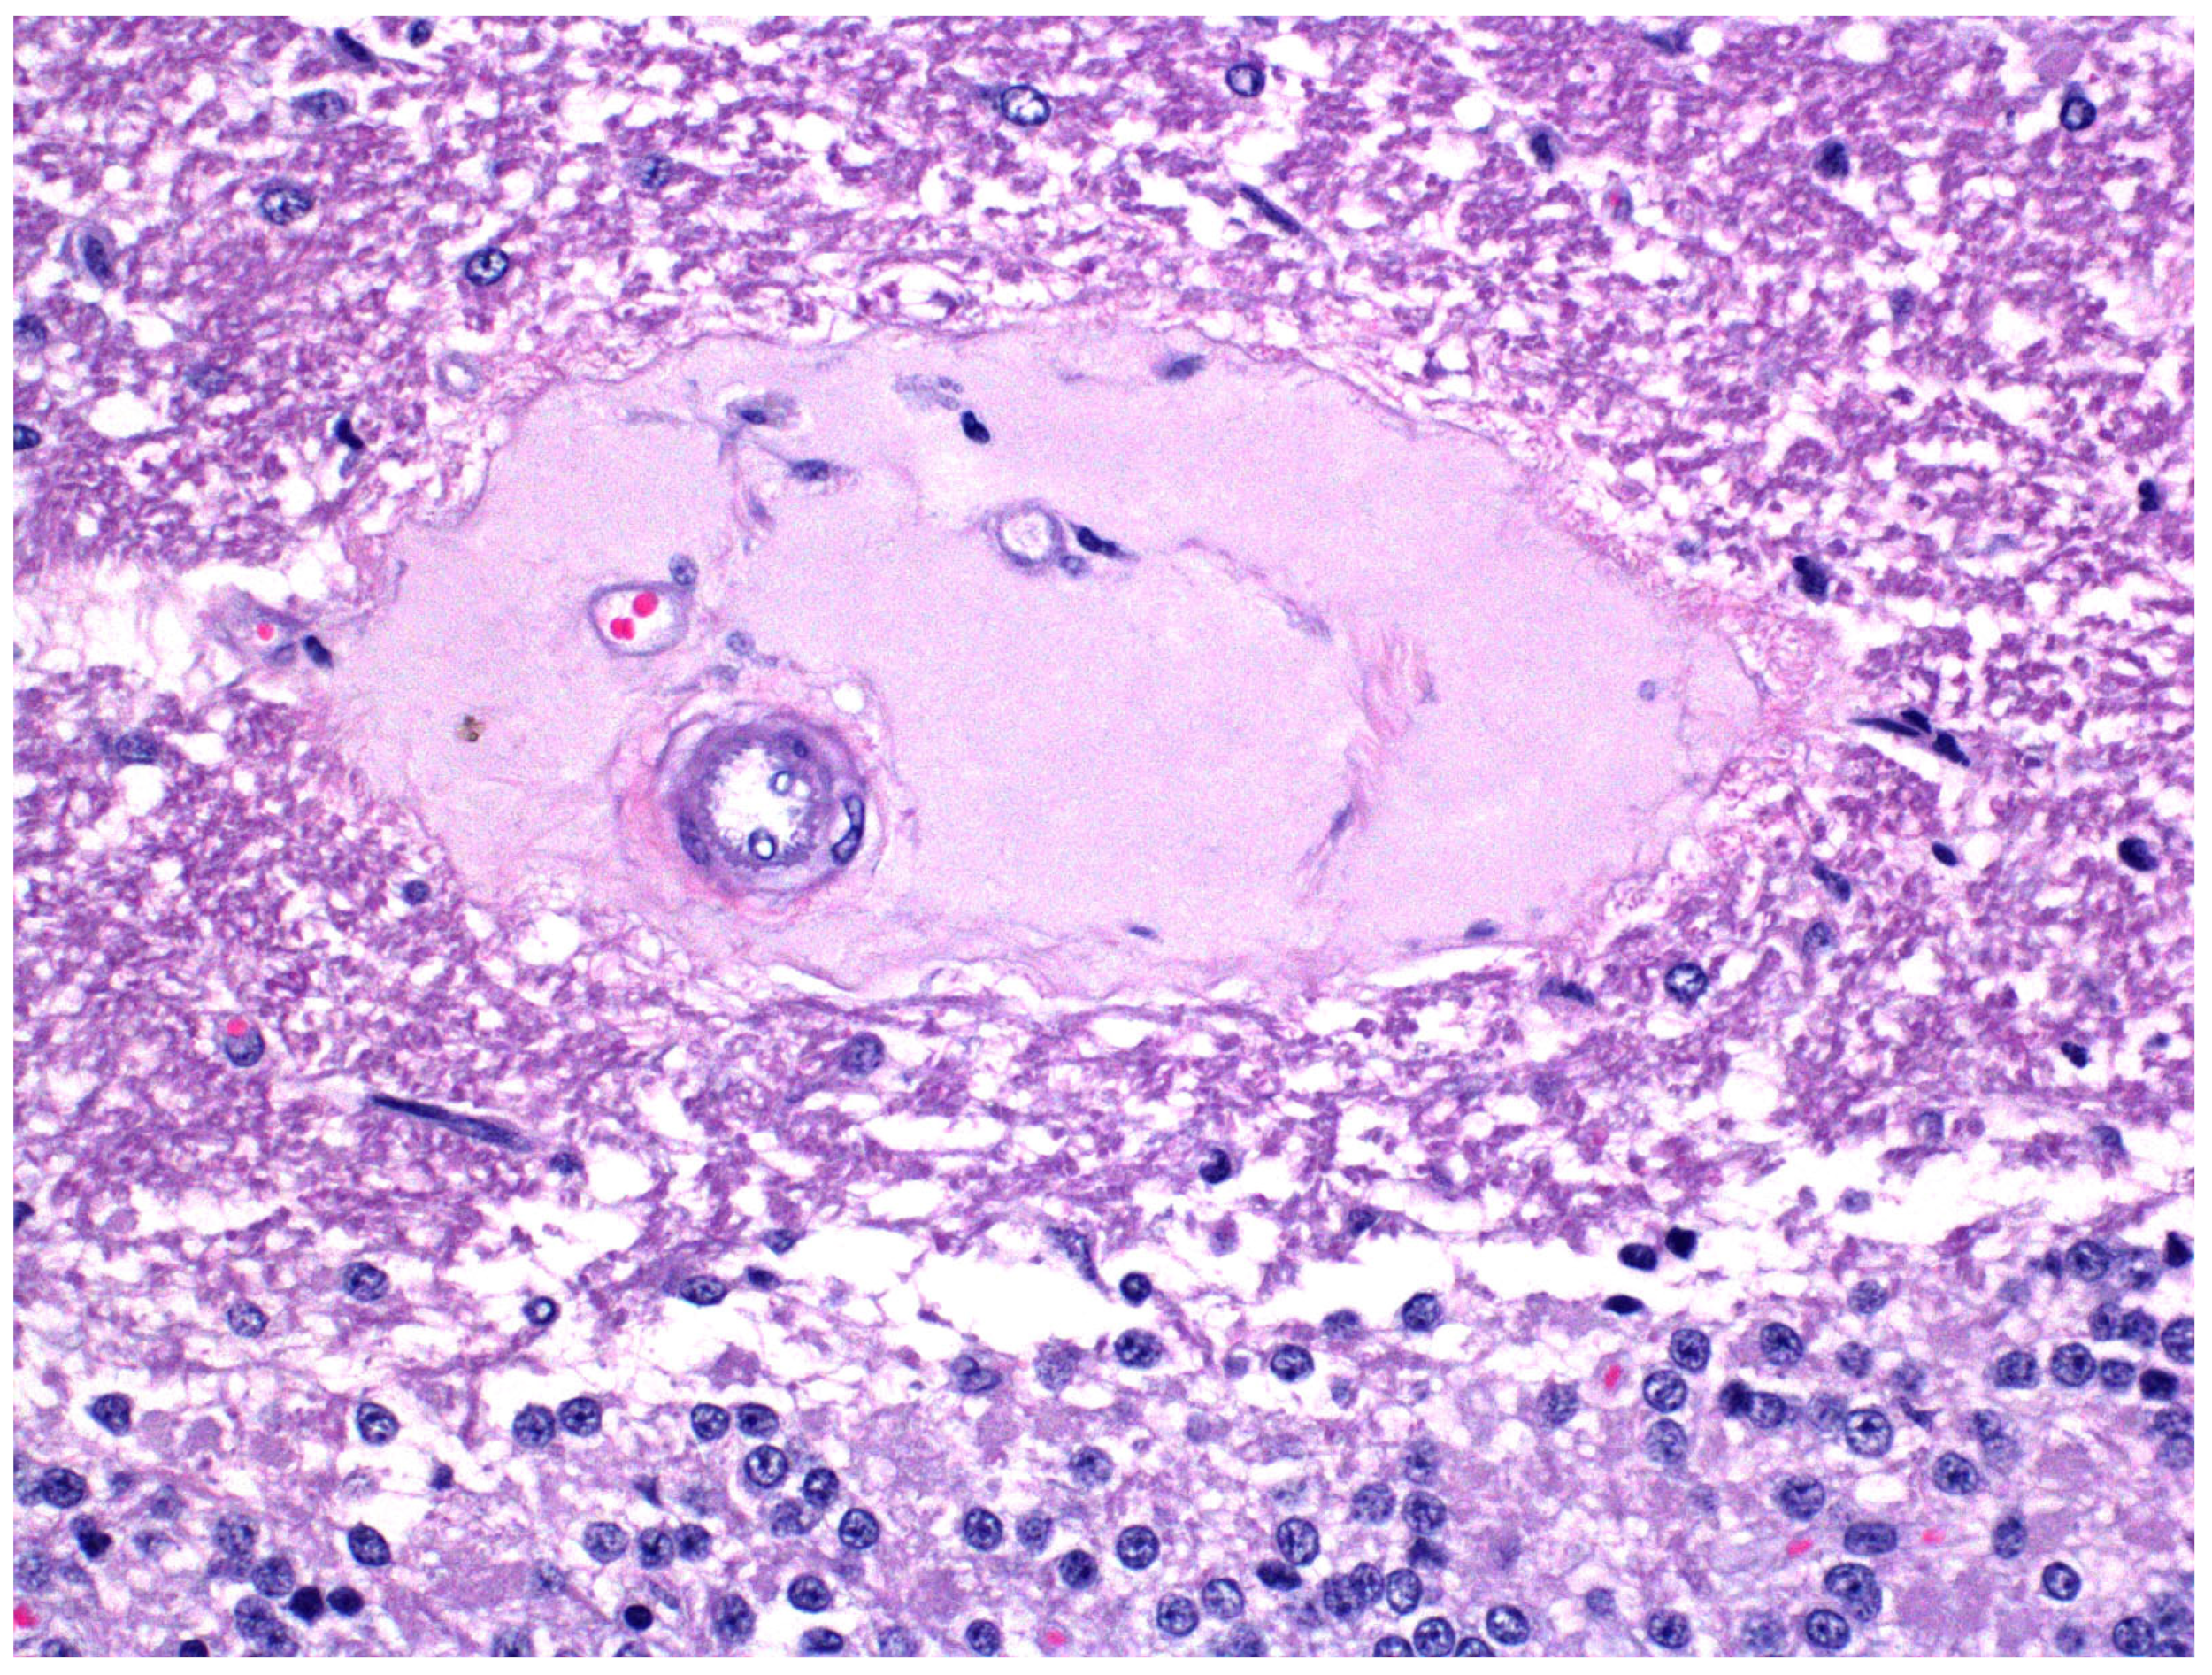

- Ortega, J.; Verdes, J.M.; Morrell, E.L.; Finnie, J.W.; Manavis, J.; Uzal, F.A. Intramural vascular oedema in the brain of goats with Clostridium perfringens type D enterotoxaemia. Vet. Pathol. 2019, 56, 452–459. [Google Scholar] [CrossRef]

- Uzal, F.A.; Glastonbury, J.R.; Kelly, W.R.; Thomas, R. Caprine enterotoxemia associated with cerebral microangiopathy. Vet. Rec. 1997, 141, 224–226. [Google Scholar] [CrossRef]